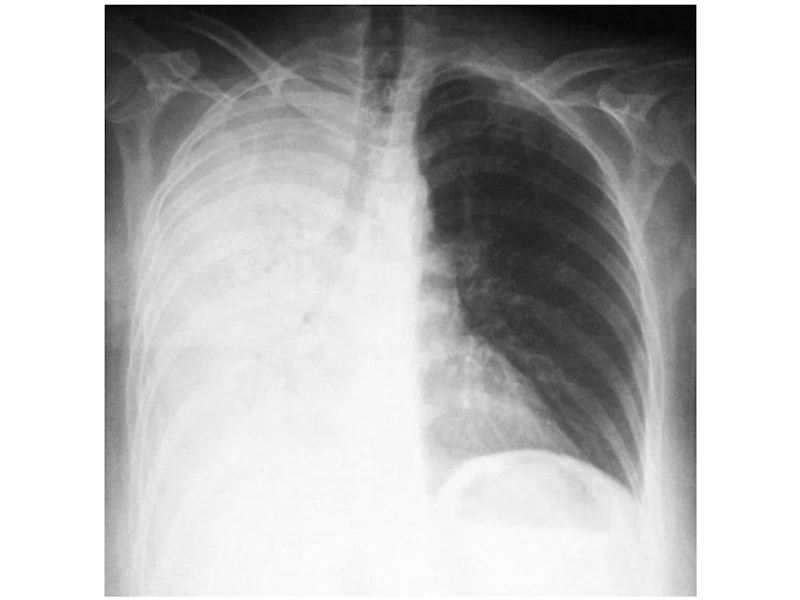

Слайд 61Правосторонний плеврит

Правосторонний плеврит